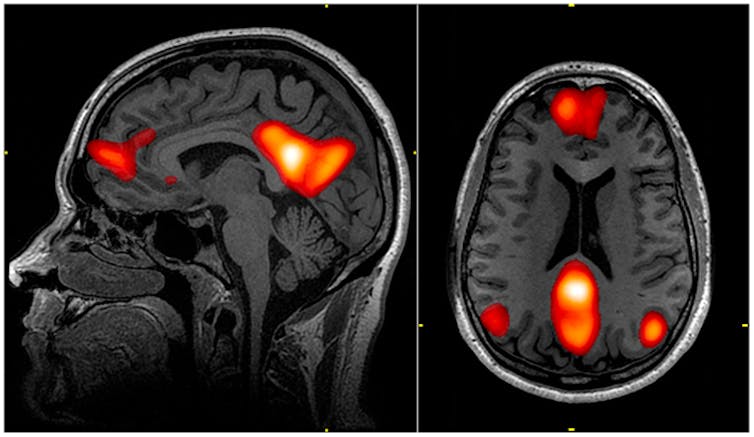

When we experience boredom – say, while watching a movie – our brain engages specific networks. The attention network prioritises relevant stimuli while filtering out distractions and is active when we commence the movie.

However, as our attention wanes, activity in the attention network decreases, reflecting our diminished ability to maintain focus on the unengaging content. Likewise, decreased activity occurs in the frontoparietal or executive control network due to the struggle to maintain engagement with the unengaging movie.

Simultaneously, the default mode network activates, shifting our attention toward internal thoughts and self-reflection. This is a core function of the default mode network, referred to as introspection, and suggestive of a strategy for coping with boredom.

This complex interplay of networks involves several key brain regions "working together" during the state of boredom. The insula is a key hub for sensory and emotional processing. This region shows increased activity when detecting internal body signals – such as thoughts of boredom – indicating the movie is no longer engaging. This is often referred to as "interoception".

The amygdala can be likened to an internal alarm system. It processes emotional information and plays a role in forming emotional memories. During boredom, this region processes associated negative emotions, and the ventral medial prefrontal cortex motivates us to seek alternative stimulating activities.